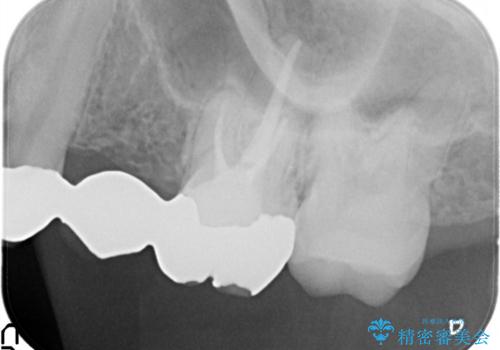

- 保険治療で装着されたかぶせ物と詰め物を変更したいとのことで来院されました。

自然なオールセラミックへ変更することとなりました。

金属を使わないセラミックへ変更することで、自然な見た目になるとともに、ぴったりとした精度の高いかぶせ物を装着することができました。